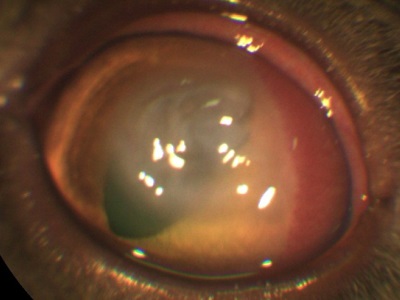

De exemplu, atunci când bariera este lovit stratul lichid intern al corneei - endoteliului. Unele rase de câini au o predispoziție genetică la o scădere a numărului de celule endoteliale, care este motivul pentru care se umfla corneei si devine alb. De asemenea, în cazul în care numărul acestor celule este prin natura prea puține animale, dar cu varsta ele devin chiar mai mici.

În acest context, se poate dezvolta edem excesiv de puternic, separarea corneei, formarea de bule specifice (Bull).

Sau fara celule endoteliale daunatoare

Tratamentul tuturor acestor patologii extrem de variably și include tratamentul medicamentos și chirurgical (plastic cornee, tarzorrafiya impact termic) depinde de starea ochiului.